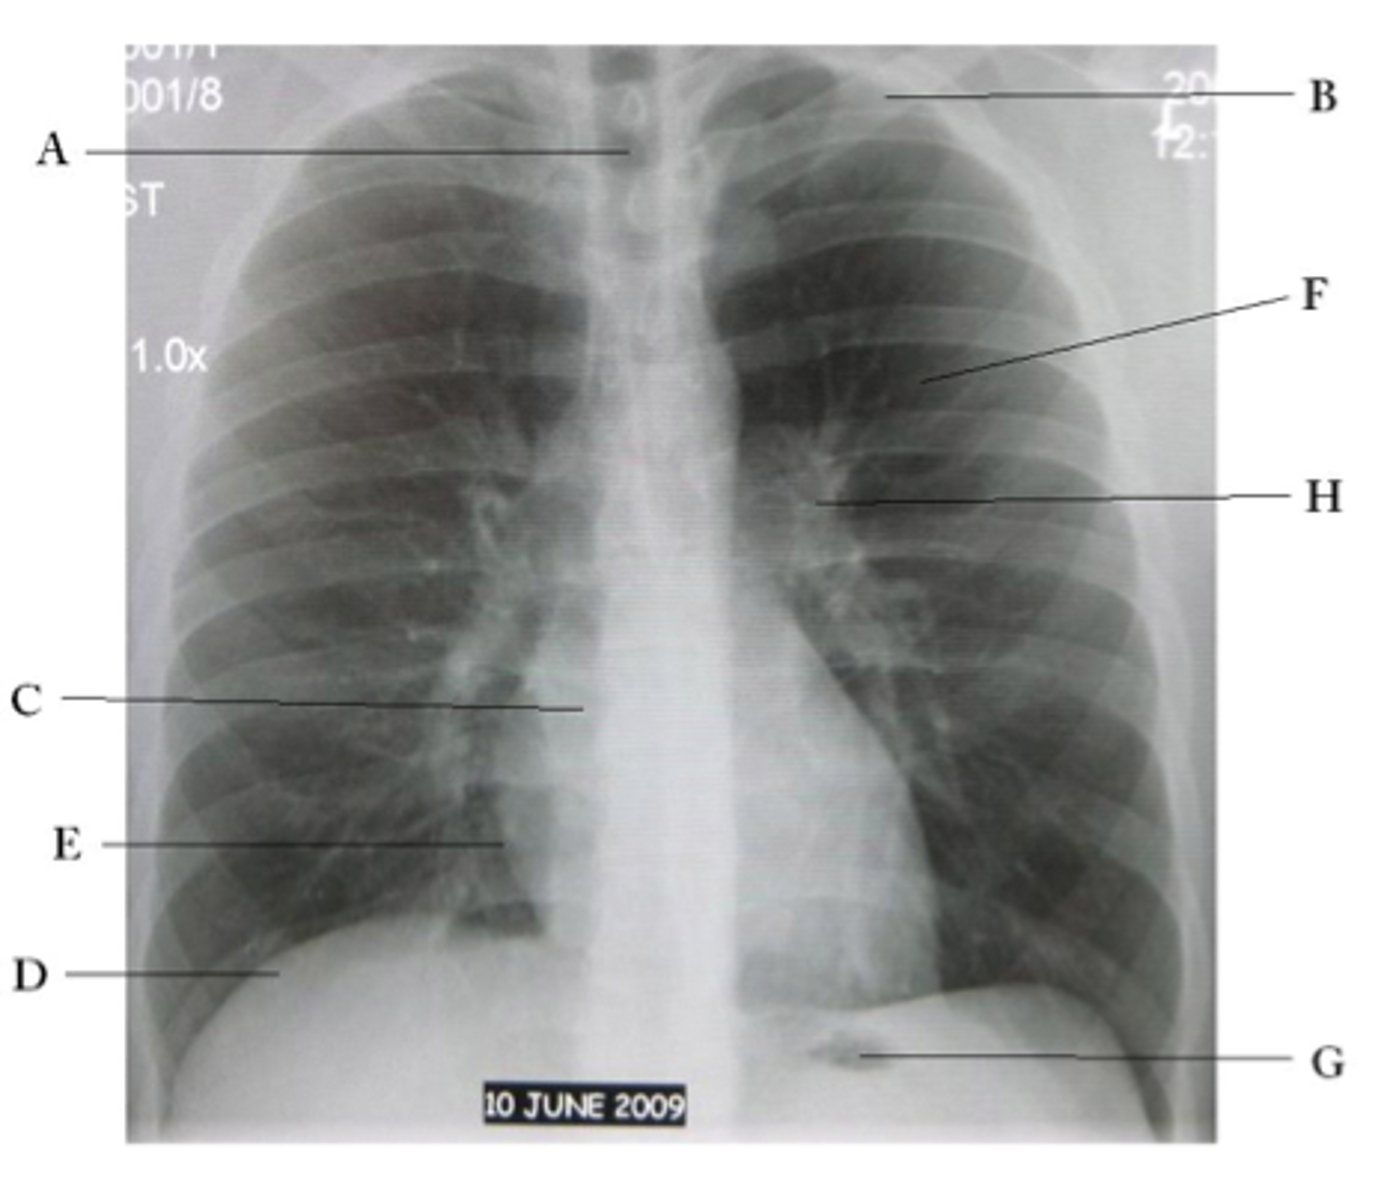

A

trachea

B

Clavicle

C

Right atrium

D

Diaphragm

E

Cardiophrenic angle

F

left upper lobe

G

gastric bubble

H

Left hilum